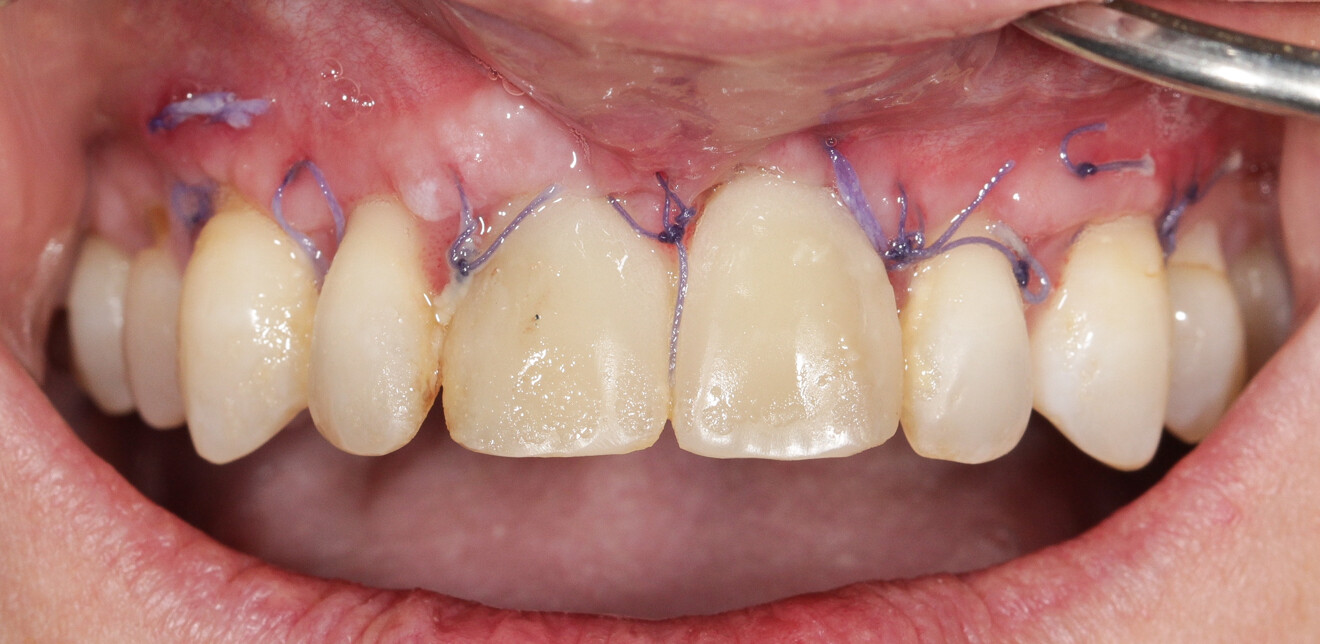

Nous réalisons un lambeau avec une incision crestale décalée en palatin en 11 et 21, sulculaire en 12, 13, 22, 23, en prenant soin de préserver les papilles interdentaires, ainsi que deux décharges verticales en distal des canines. Nous réalisons un décollement de pleine épaisseur (Figs. 28 et 29). Les dents (12, 22 et 18) sont facilement extraites et les alvéoles curetées avec soins. Deux implants (4*13) sont positionnés dans la paroi palatine des alvéoles, il subsiste une déhiscence vestibulaire en 22. Les racines de 12, 22 et 18 sont séparées dans le sens de la longueur. Les racines préparées comme indiqué ci-dessus, sont vissées en vestibulaire et en occlusal de la crête, au moyen de vis d’ostéosynthèse (diamètre 0,9 mm), afin de reconstruire la crête osseuse au niveau des inters de bridge ainsi que la paroi vestibulaire de la crête au niveau de 22 (Figs. 30 et 31). Le gap vestibulaire entre les implants et la crête ainsi que l’espace entre la crête et le greffon au niveau de 21, sont comblés avec un matériau d’origine synthétique (Collapat II Symatese). Le lambeau est tracté, suturé coronairement avec un fil tressé synthétique 5.0 (Fig. 32). Des piliers coniques droits pour prothèse plurale transvissée sont posés, et une empreinte prise à la fin de l’intervention (Fig. 33). Un provisoire est réalisé dans la journée par notre laboratoire de prothèse et posé le soir même. (Figs. 34 et 35)